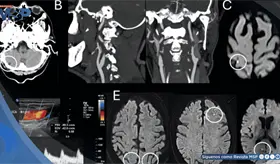

Las imágenes sugirieron un tumor con hueso, grasa y tejido cerebral dentro del recto, confirmando un diagnóstico poco común que solo se documenta en uno de cada 35.000 a 40.000 casos a nivel mundial.